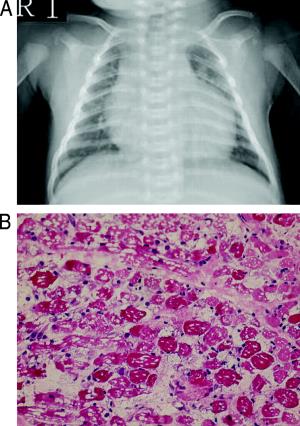

Klasičan oblik infantilne pojave (početka) Pompeove bolesti počinje u roku od nekoliko meseci nakon rođenja. Deca sa ovim poremećajem obično iskuse sledeće simptome: slabost mišića (miopatija), slab tonus (hipotonija), uvećanu jetru (hepatomegalija) i srčane mane. Pogođena deca mogu takođe da ne dobijaju na težini i ne rastu očekivanom stopom (prekid u razvoju) i imaju problema sa disanjem. Ukoliko se ne leči, Pompeova bolest u ovom obliku dovodi do smrti od srčane insuficijencije u prvoj godini života.

Ne-klasičan oblik infantilne pojave Pompeove bolesti obično se javlja od starosti od 1 godine. Odlikuje se odloženim motoričkim sposobnostima (kao što je prevrtanje i sedenje) i progresivnom mišićnom slabosti. Srce može biti neuobičajeno veliko (kardiomegalija), ali ugroženi pojedinci obično ne doživljavaju srčani udar. Slabost mišića u ovom poremećaju dovodi do ozbiljnih problema sa disanjem, a većina dece žive samo u ranom detinjstvu.